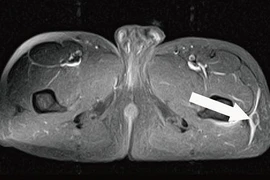

(khoahocdoisong.vn) - Trường hợp vỡ xương chậu phức tạp, đặc biệt là gãy phần sau như gãy vùng cánh chậu và cùng cụt kết hợp với tình trạng lóc da vùng hông lưng... được gọi là tổn thương Morel Lavalleé.